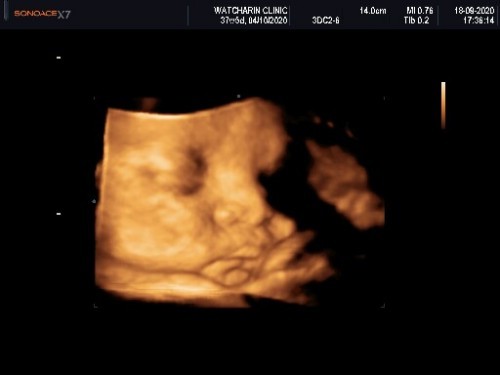

มาอวดรูปตอนซาวด์กันหน่อยค่ะ แม่ๆกำหนดคลอดเดือนไหนบ้างคะ